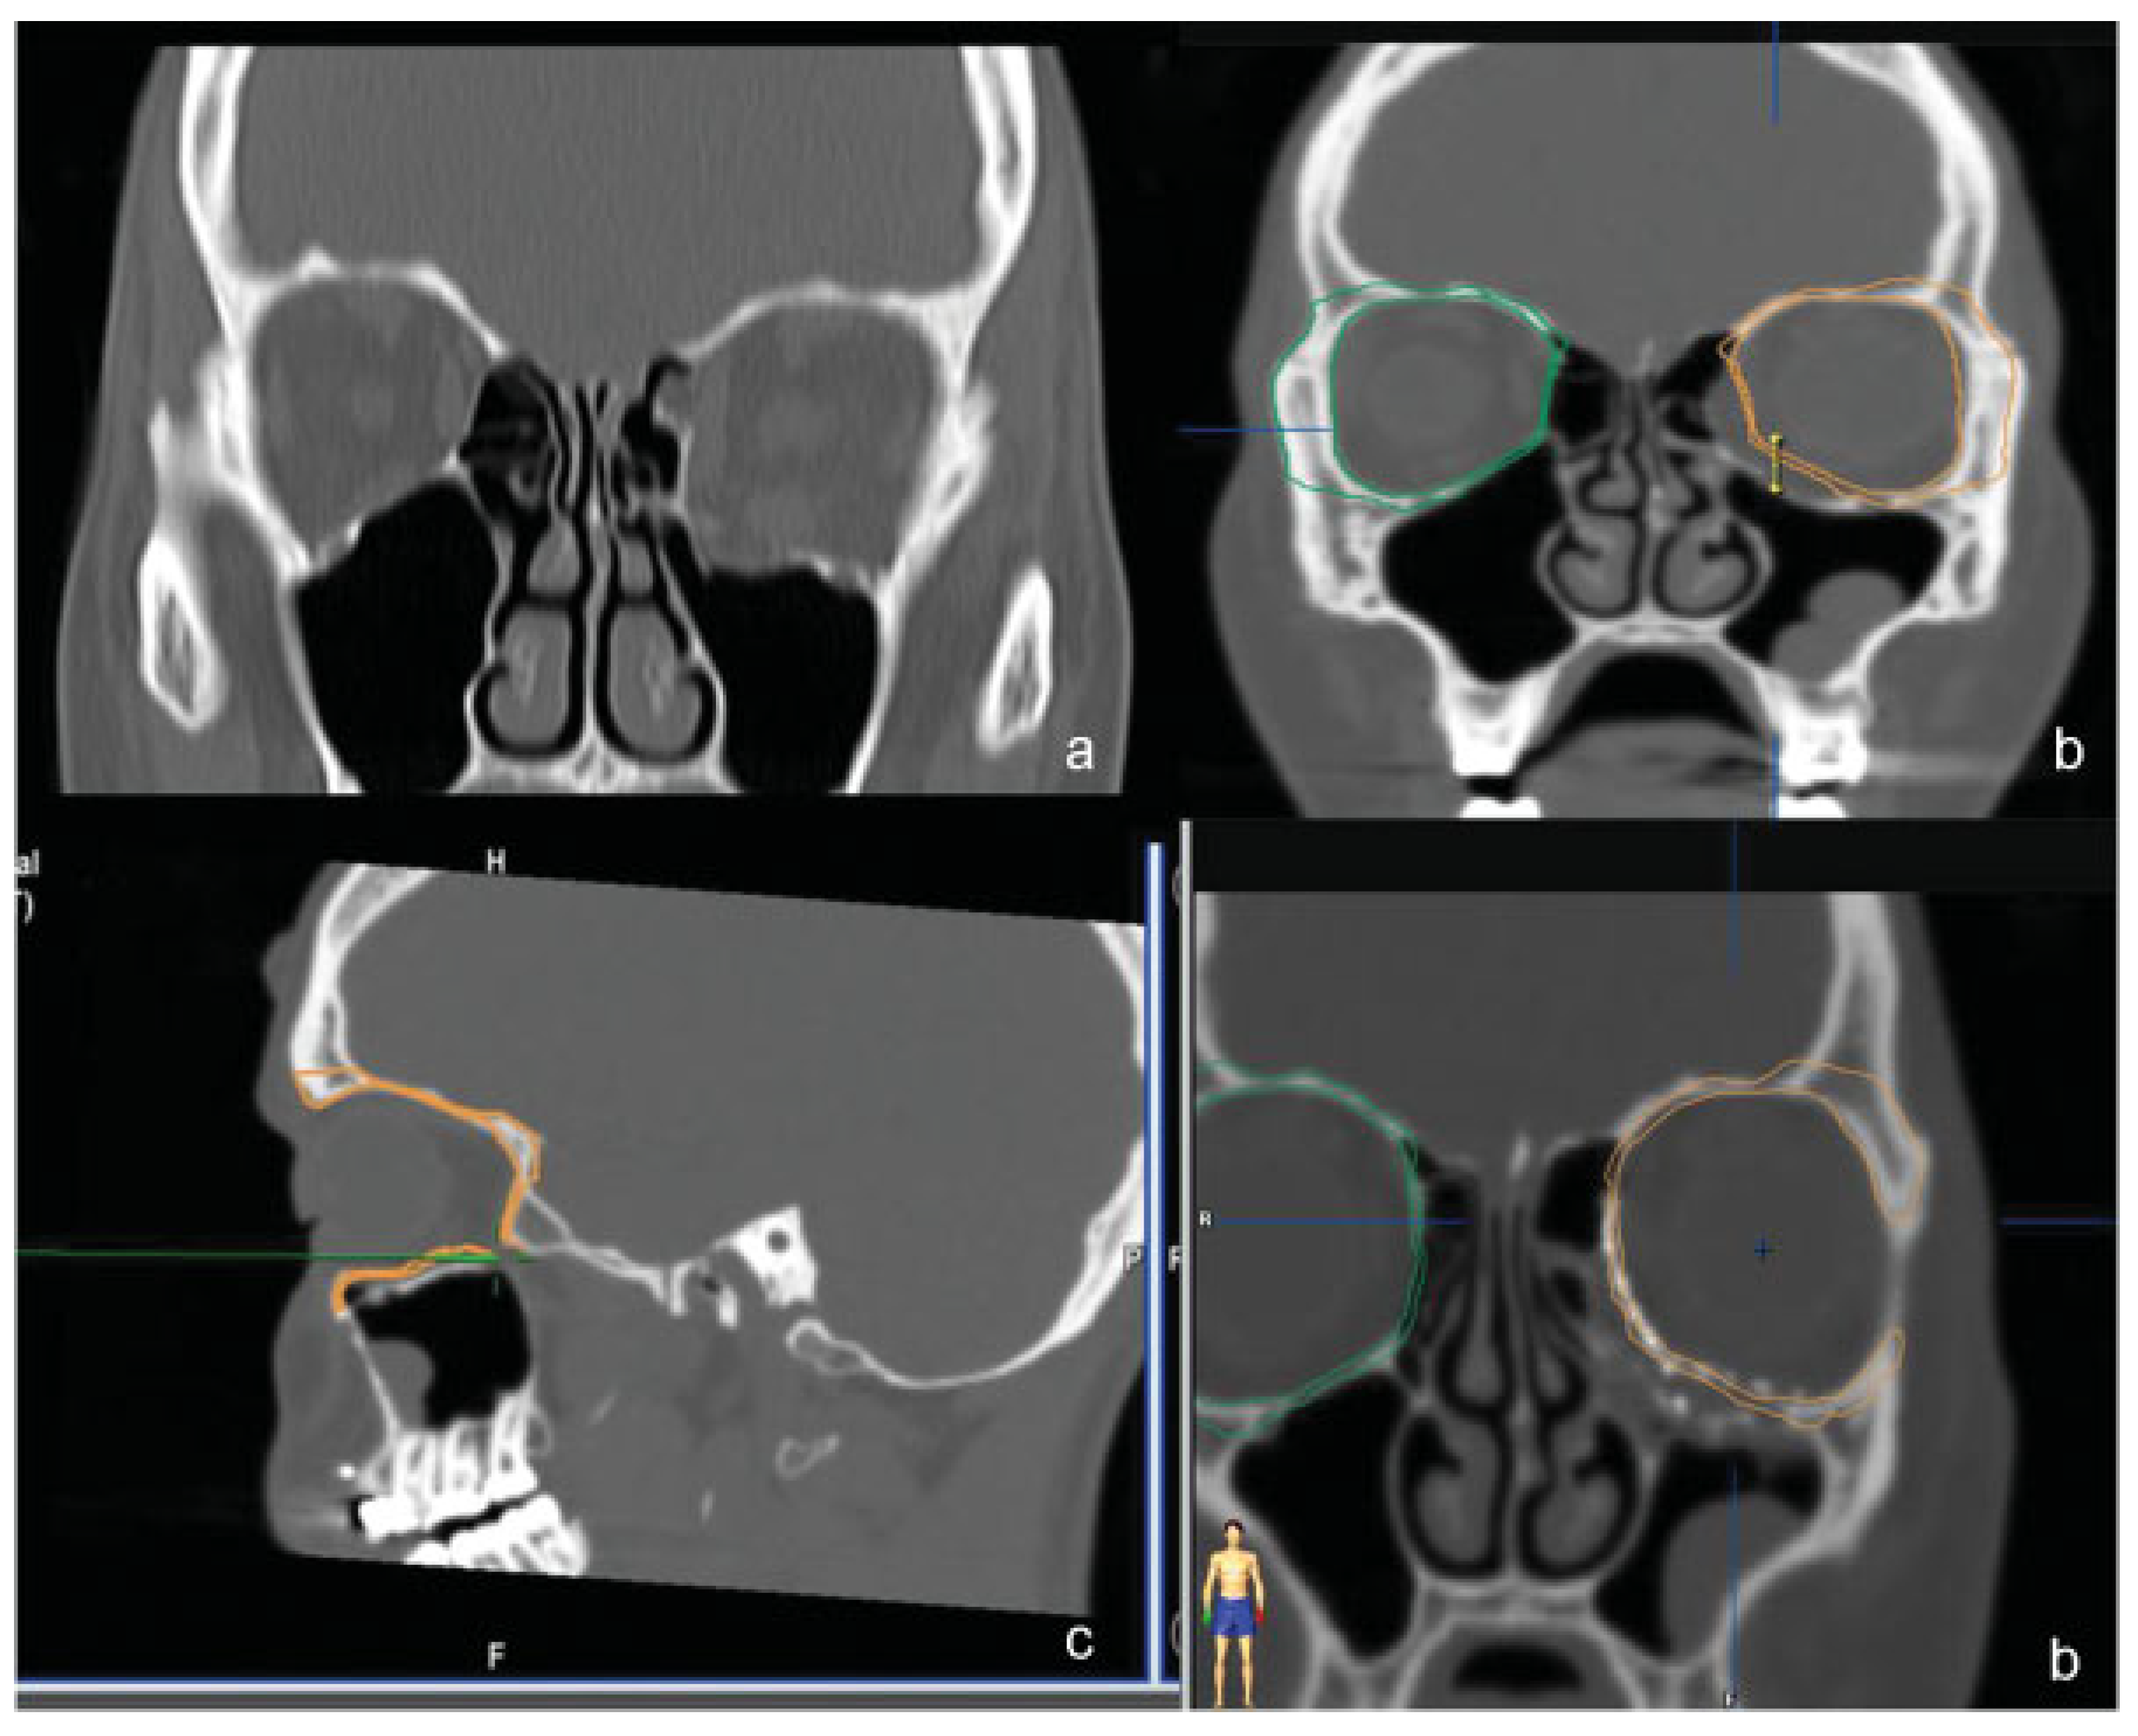

Mirroring of the unaffected orbit into the fractured side, a virtual template to simulate the ideal reconstruction was created. This template was navigated during surgery, and navigation was used both to verify the posterior ledges of the fracture and the position and shape of the implant relative to the correct anatomic position of the native bone.

In group 3 (NAVI), navigation-assisted orbital reconstruction was performed. At the time of surgery, navigation was used to assess the accuracy of dissection confirming that we have reached the posterior ledges of the fracture and the position and shape of the implant, according to virtual planning (Figure 6).

In our study, navigation-assisted orbital reconstruction is reliable in restoring orbital shape and volume. We totally agree with Markiewicz et al. [11] and Bly et al. [9] that navigation-aided surgery improves outcomes in complex orbital reconstruction.

Figure 6. Group 3 (NAVI). Navigation-aided orbital repair in combined medial wall/floor orbital fracture. (a) Preop image. (b) Computer-assisted planning and creation of a virtual template. (c) Identification of posterior ledge of the fracture and limit of dissection in apical direction. (d) Postop image fusion and control.